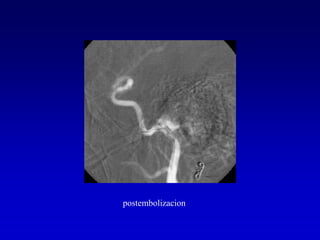

Caso 3

postembolizacion